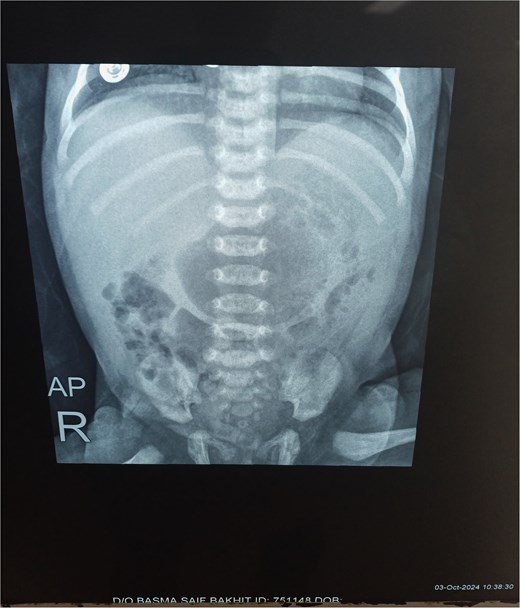

Chest X-ray was normal (Fig. 1). A water-soluble contrast meal was performed (Fig. 2) and the contrast arrested at the gastric antrum for 45 min. Then there was normal opacification of the duodenum and jejunum on follow-up films after 1.15 and 1.3 h. A complementary ultrasound (US) was done along with the contrast study and it showed a thick mucosal fold (4 mm) at the gastric antrum situated 1 cm away and on the left side of the duodenum. The pyloric canal was open and patent and had a normal wall thickness (1.5 mm) excluding hypertrophic pyloric stenosis.